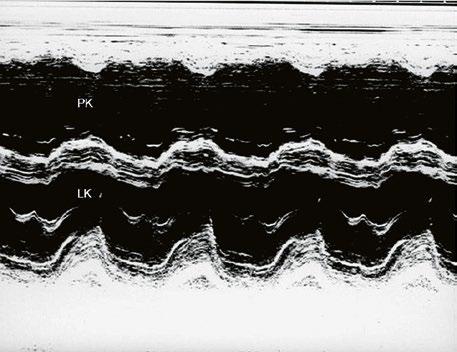

Obr. 45.9 M mode, paradoxní pohyb septa při objemovém přetížení pravé komory u defektu septa síní typu II s levopravým zkratem

Zkrat na úrovni síní bývá levopravý kvůli vyšší compliance pravé komory. Dochází k objemovému přetížení pravé komory, zvýšenému plicnímu průtoku a hyperkinetické plicní hypertenzi. Plicní cévní rezistence bývá v dětství a mládí většinou normální, ve vyšším věku může být mírně zvýšená. V dilatované plicnici mohou vznikat tromby in situ, s možnou distální embolizací, případně může dojít i k paradoxní embolizaci do systémového řečiště. Levá komora je méně plněná, utlačená dilatovanou pravou komorou. Při dilataci trikuspidál

Poslechový nález systolického šelestu nad plicnicí s fixním rozštěpem 2. ozvy je nenápadný. Echokardiograficky je patrná dilatovaná a objemově přetížená pravá komora s paradoxním pohybem septa (Obr. 45.9), zkratový tok může být vidět i transtorakálně (TTE) (Obr. 45.10, Video 45.3, Video 45.7), ale suverénní diagnostickou metodou je jícnová echokardiografie (TEE), případně s 3DE zobrazením (Obr. 45.1, Obr. 45.2,